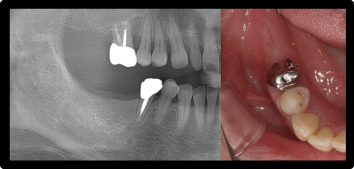

奥歯のインプラントの症例

ブリッジが壊れて奥歯を失った方

BEFORE

AFTER

症例概要

年代・性別

40歳代 女性

主訴

奥歯がグラグラする

治療内容

下顎両側6番 インプラント治療、左下5番セラミッククラウン(デジタル)

治療期間

3ヶ月

治療のリスク

インプラント周囲炎のリスクがあるため、メンテナンスに来ていただきます。

治療費用

913,000円(税込)